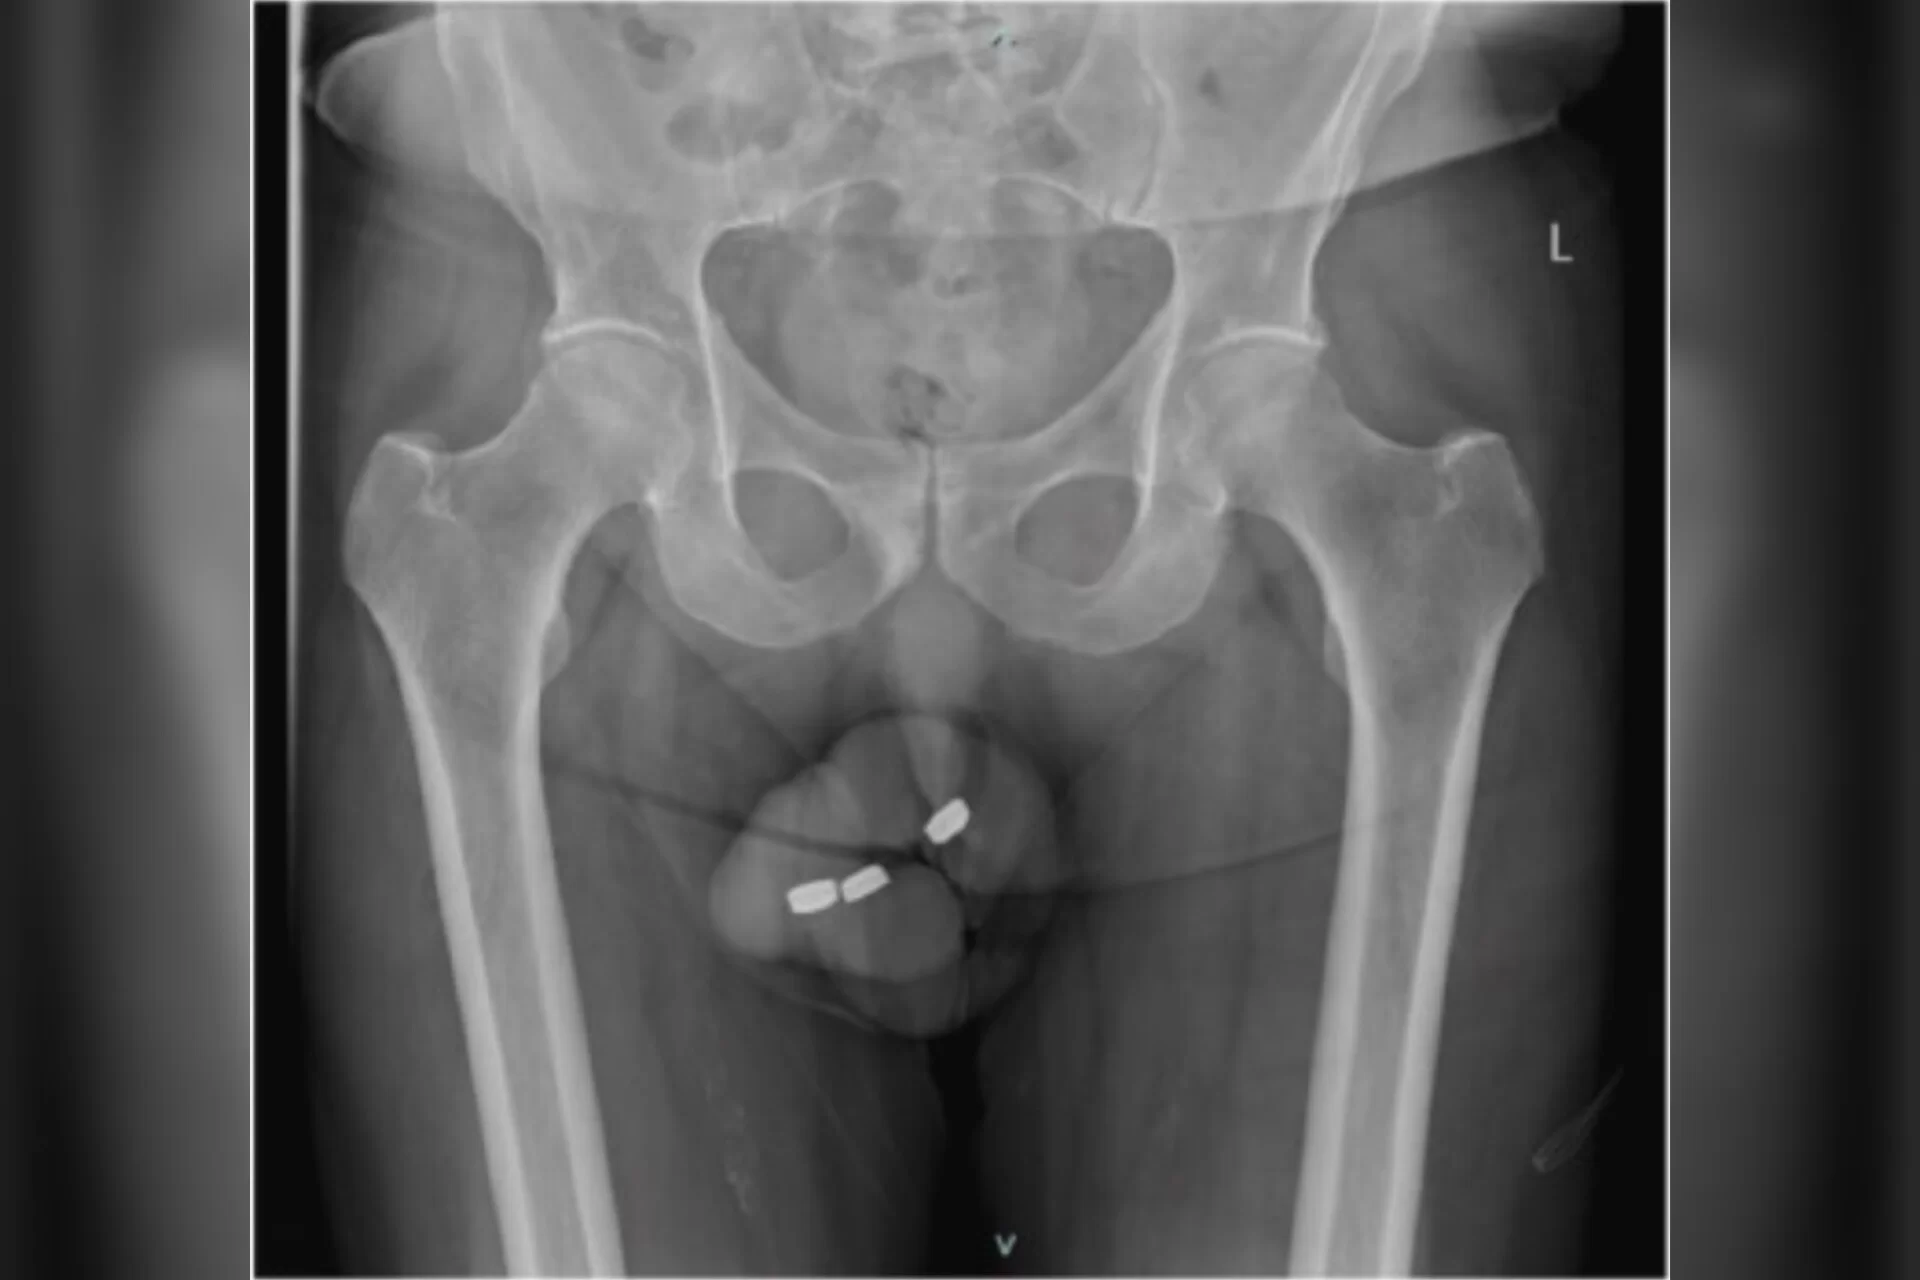

Idoso com impotência coloca baterias de relógio no pênis e vai...

AUSTRÁLIA - Um idoso acabou indo parar num hospital australiano com fortes dores no p3nis, onde foi descoberto que havia 3 unidade de baterias...